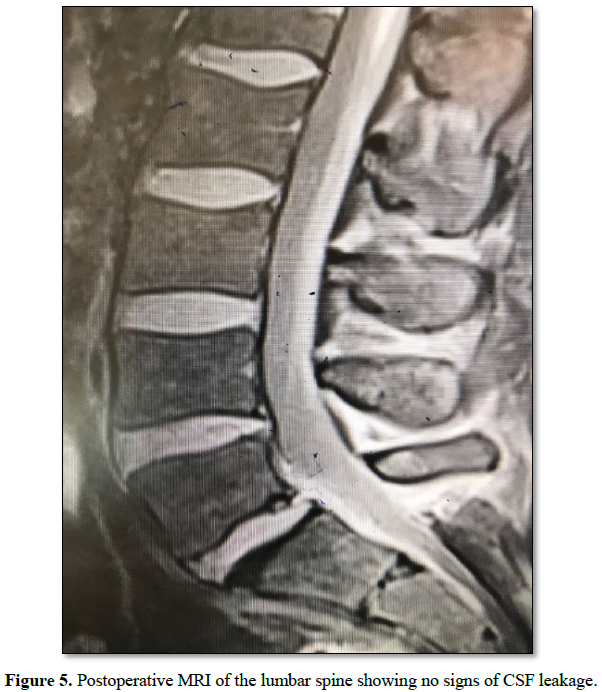

The patient was kept on flat bed rest for 24 h after which

he was allowed to ambulate freely. He did not report any symptoms related to

CSF leakage like headache, nausea, vomiting or neck pain and stiffness. A

two-week follow up MRI of the lumbar spine showed no signs related to CSF

leakage (Figure 5).